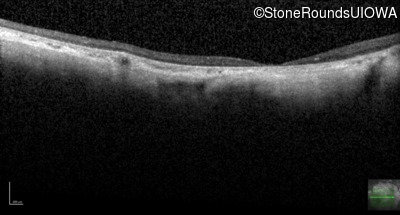

Optical Coherence Tomography - Right - Unable to Quantify

Exemplar / OCT Stack

OCT Stack